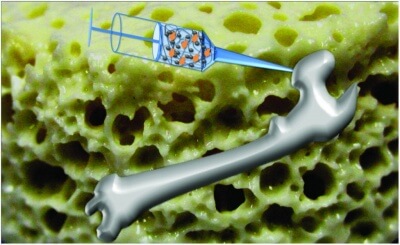

Замещение дефектов костной ткани у животных

Тканевая инженерия